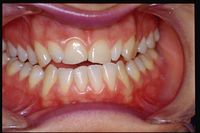

Figure 2: Oral situation of the patient affected by TMDs showing the ant erior cross bite

As usual, we call our patient with a fancy name and precisely 'Clicker' because the patient had been suffering from temporomandibular joint (TMJ) clicks for years. Clicker presented to our neuropathology department complaining of severe orofacial pain and reporting a chronic right TMJ joint removal. She arrived after having already been diagnosed as DTMs always following the RDC protocol and treated with a biteplane to manage the nocturnal teeth grinding only. She, a 40-year-old patient who reported orofacial pain with joint noises such as clicks and crashes on both sides of the face and difficulty in chewing.

A first clinical occlusal examination shows a functional occlusal class III with sliding in protrusion in reaching the maximum intercuspidation. On palpation, the masseters, temporals, and external pterygoids on both sides were tender. No balance and gait disturbances, no vertigo, no tinnitus but as our routine we immediately performed trigeminal electrophysiological tests in order to avoid any structural involvement of the trigeminal Central Nevous System (tNCS). As already explained in the chapter concerning the 'Balancer' patient with Meningioma in which the interference EMG examination performed by the dental colleagues did not give indications of organic pathology of the tNCS in our Diagnostic Center we only perform Evoked Potentials and the battery of trigmeinal reflexes. In this chapter, taking into account the clinical situation, we have bypassed the purely dental context as, after an initial objective examination, the malocclusive disorder is striking but not certain (figure 2).